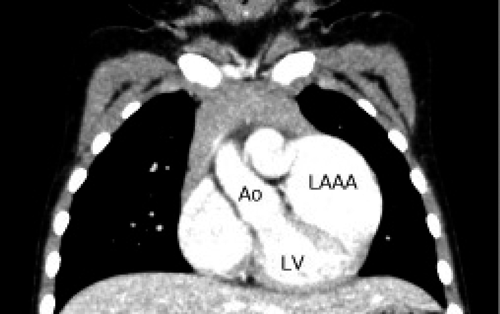

無症候性左心耳瘤の病理組織学的検討Histopathological Findings of Asymptomatic Left Atrial Appendage Aneurysm